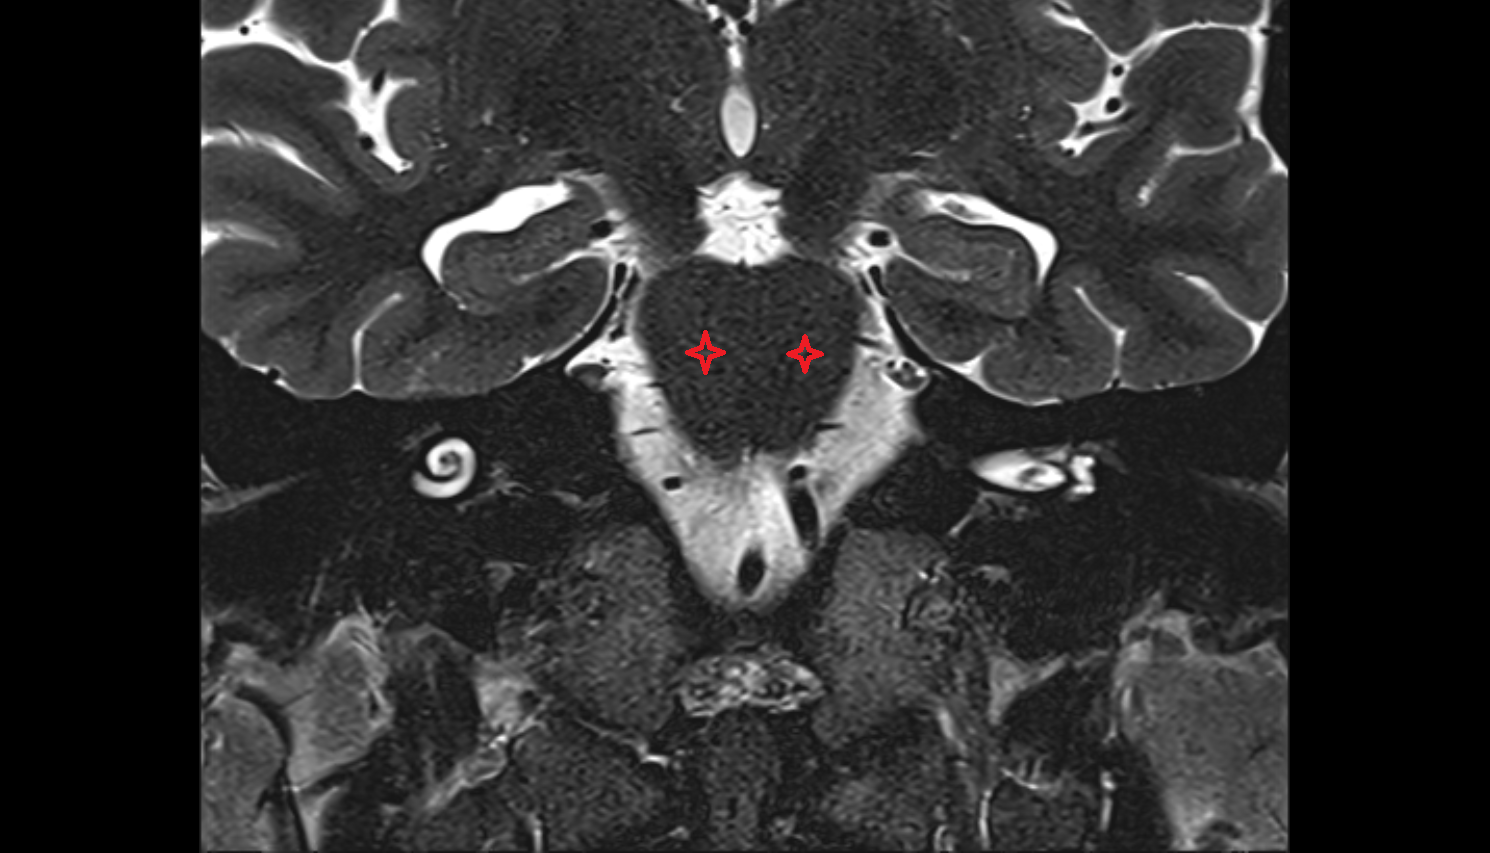

- Dentate nucleus